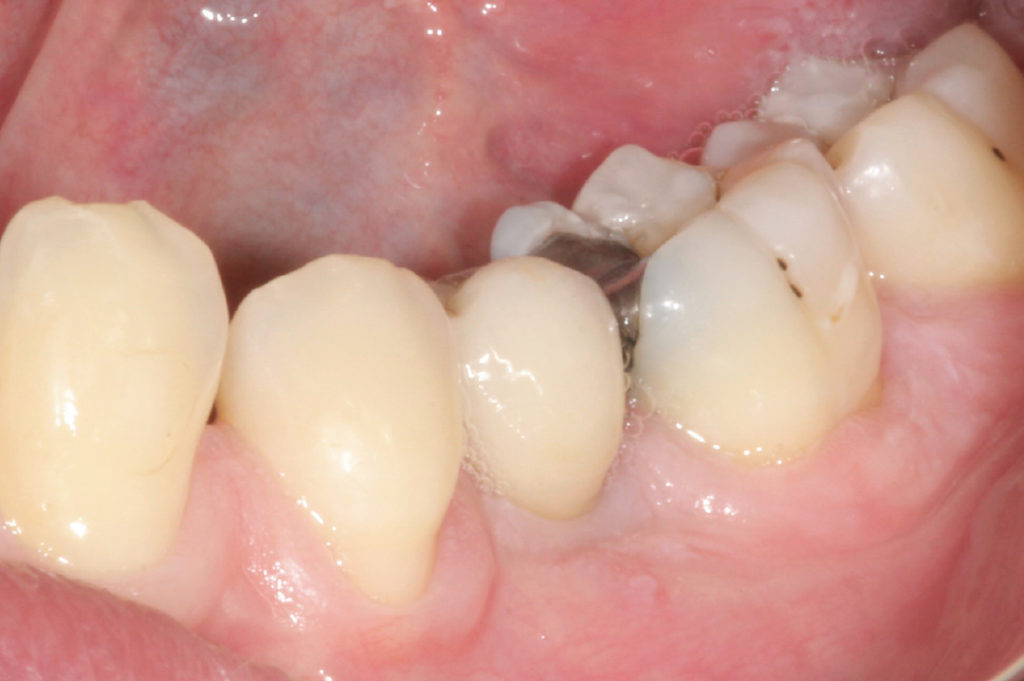

Vista del diente #25 siete años después de la inserción

Vista del diente #45 siete años después de la inserción

Vista del diente #35 siete años después de la inserción